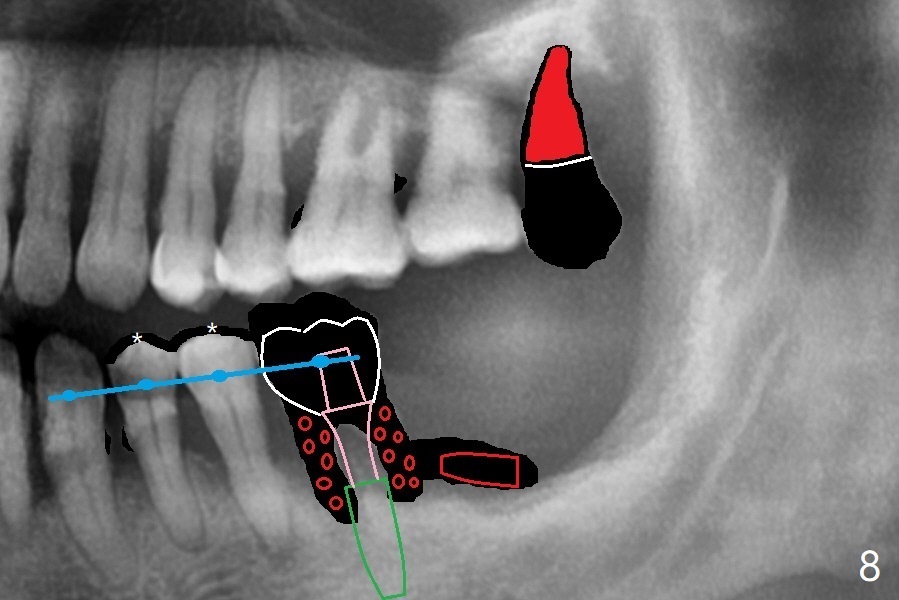

56岁男几十年拒绝牙周炎治疗,也不愿意拔除所有牙齿做全口植牙修复。17,18号牙自行脱落,现在要求拔除16,19;18,19种植(图一),后者牙龈厚(双箭头),但是18号牙骨质高度不足(图二),勉强植入5x7.3毫米植体。15,16骨质吸收严重(图三),16,19拔除,局部深洗后(图四:黑色),为了延长15号牙使用期,16号牙牙槽窝植骨(图五:红色)。19号牙种植徒手,因为邻牙(包括20,21号牙))松动,做导板不准确,钻洞使用环形钻头(图六),保留骨塞(bone plug),用于18号牙骨质高度骨块移植。19号牙拔除后,往远中18牙位做潜行分离(图七:黑色)。19种植(绿色),基台(粉红色),骨粉(圆圈),临时牙冠(白色),16号牙粘性骨粉植骨(红色),PRF,Cytoplast覆盖(白线),缝合。从19号牙钻洞取来的骨塞,塞入18号牙潜行分离处(图八);利用临时牙冠和22号牙以及钢丝,树脂固定20,21号牙(蓝色),并且降低咬合(*)。最后,用螺钉固定骨塞(图九:深蓝色)。